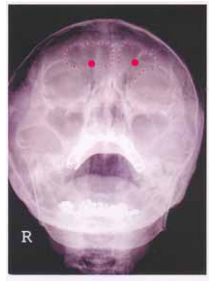

8 附圖 X 光片中,紅點所標示的結構為:(A)額竇 (B)篩竇 (C)蝶竇 (D)上頜竇